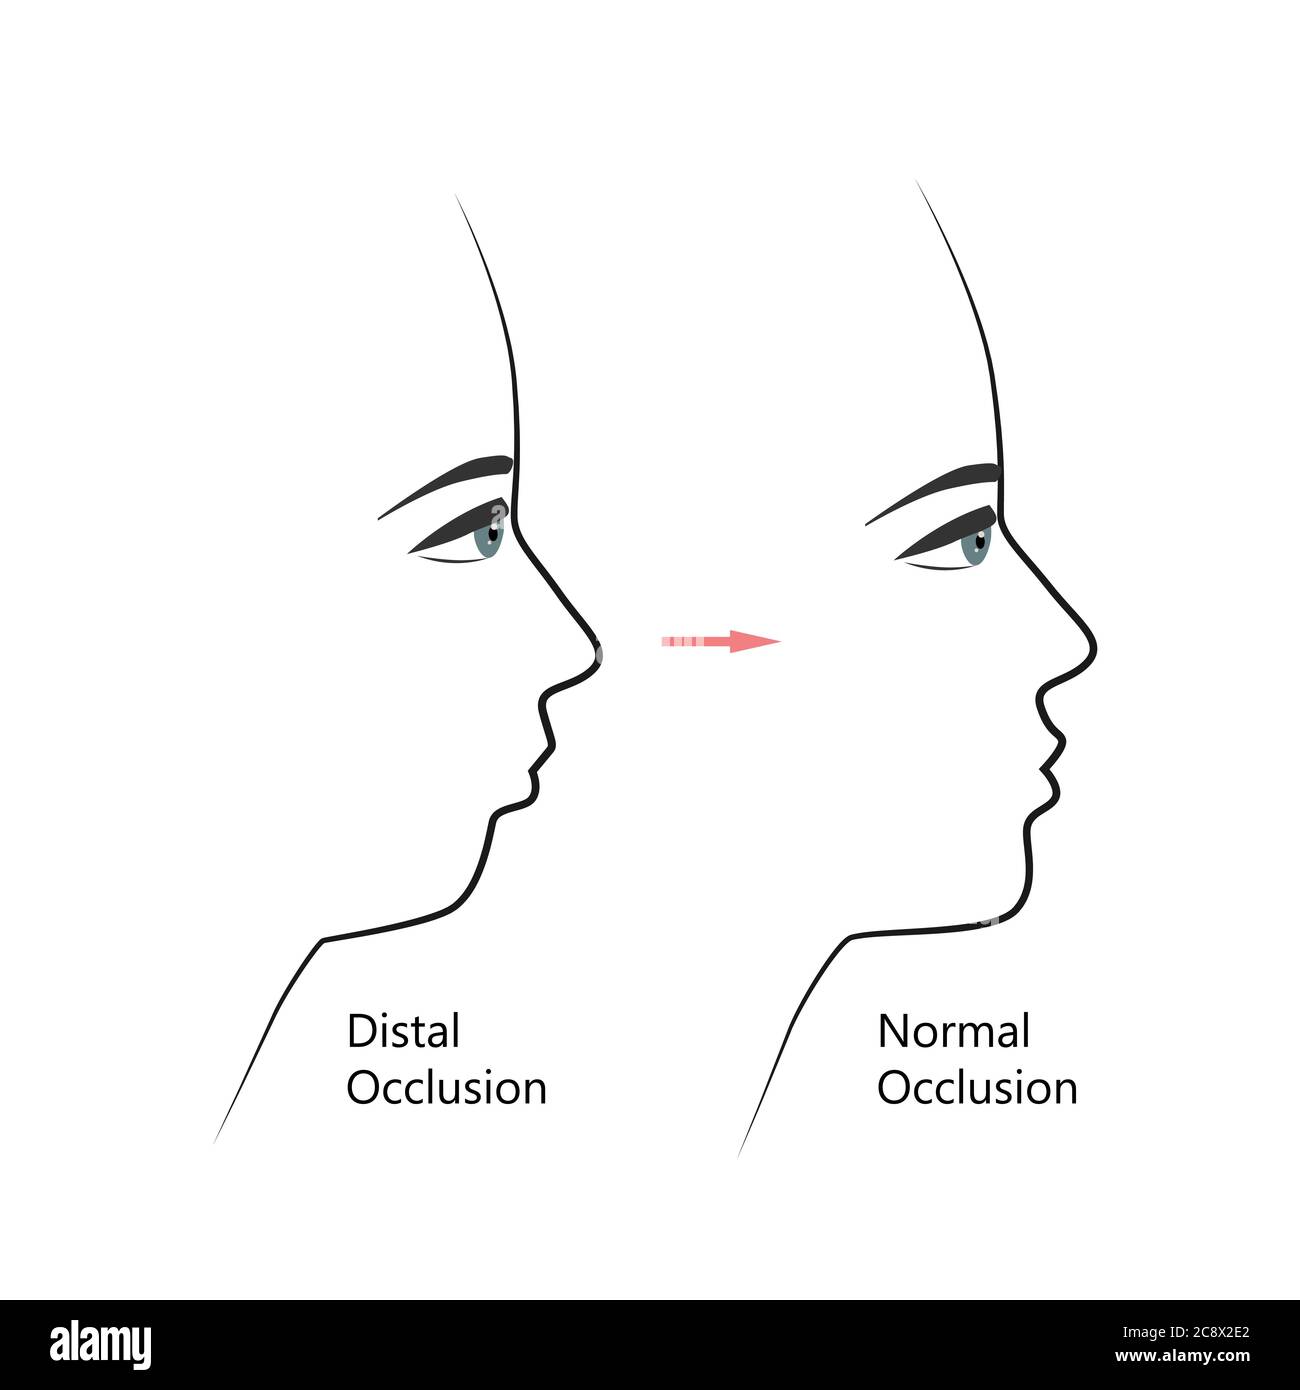

Profil distal de la morsure avant et après un traitement orthodontique. Humain présentant une malocclusion, une mâchoire inférieure repoussant, une correction de morsure par des accolades. Vecteur Illustration de Vecteurhttps://www.alamyimages.fr/image-license-details/?v=1https://www.alamyimages.fr/profil-distal-de-la-morsure-avant-et-apres-un-traitement-orthodontique-humain-presentant-une-malocclusion-une-machoire-inferieure-repoussant-une-correction-de-morsure-par-des-accolades-vecteur-image366907690.html

Profil distal de la morsure avant et après un traitement orthodontique. Humain présentant une malocclusion, une mâchoire inférieure repoussant, une correction de morsure par des accolades. Vecteur Illustration de Vecteurhttps://www.alamyimages.fr/image-license-details/?v=1https://www.alamyimages.fr/profil-distal-de-la-morsure-avant-et-apres-un-traitement-orthodontique-humain-presentant-une-malocclusion-une-machoire-inferieure-repoussant-une-correction-de-morsure-par-des-accolades-vecteur-image366907690.htmlRF2C8X2E2–Profil distal de la morsure avant et après un traitement orthodontique. Humain présentant une malocclusion, une mâchoire inférieure repoussant, une correction de morsure par des accolades. Vecteur